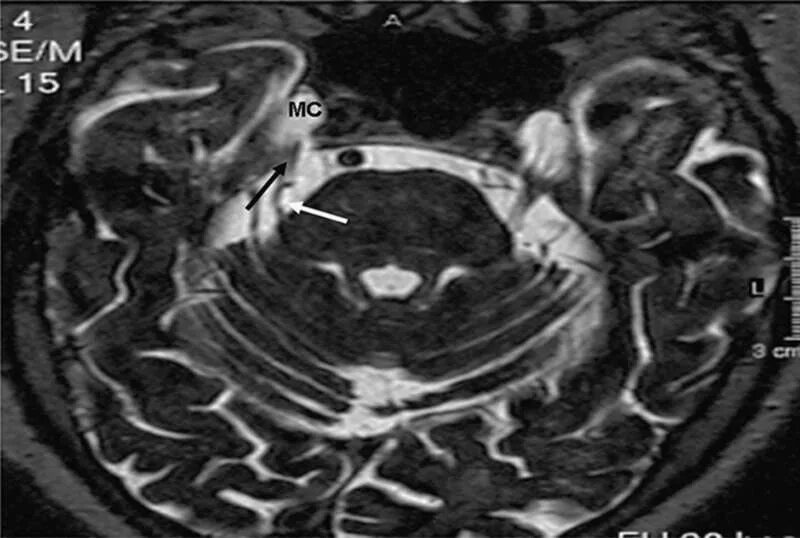

Нейроваскулярный конфликт нерва